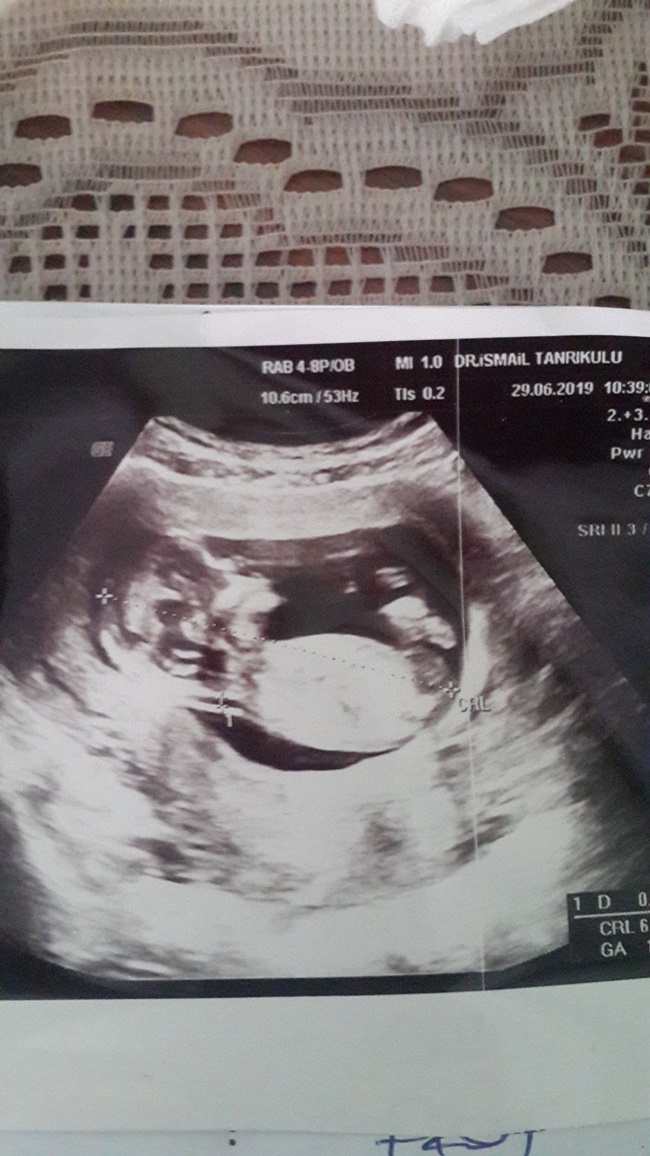

Nub teorisiyle cinsiyet tahmini bebeğim erkek mi kız mı ?

Nub teorsisi için cinsiyet tahmininde yorum isteyen arkadaşlar lütfen uyarımızı dikkate alın. Ultrason görüntüleri elinize ilk verildiği gibi net olmaz. Sık sık ışığa maruz kaldığı için görüntü kalitesi bozuluyor dolaysıyla bizlerde değerlendirme yapamıyoruz. Sizlere yorum yapabilmemiz için görüntü kalitesi aşağıdaki linkte yer alan görseller gibi olmalıdır. Ayrıca Bebeğin cinsiyeti net olarak 18-19-20. haftalarda belli olur..

Merhaba, yüklediğiniz görsellerde nub çıkıntısı anlaşılmıyor , dolaysıyla değerlendirme yapamıyoruz.. Görselin kalitesi aşağıdaki gibi olmaldır.. Sağlıklı gebelik süreci diliyorum.